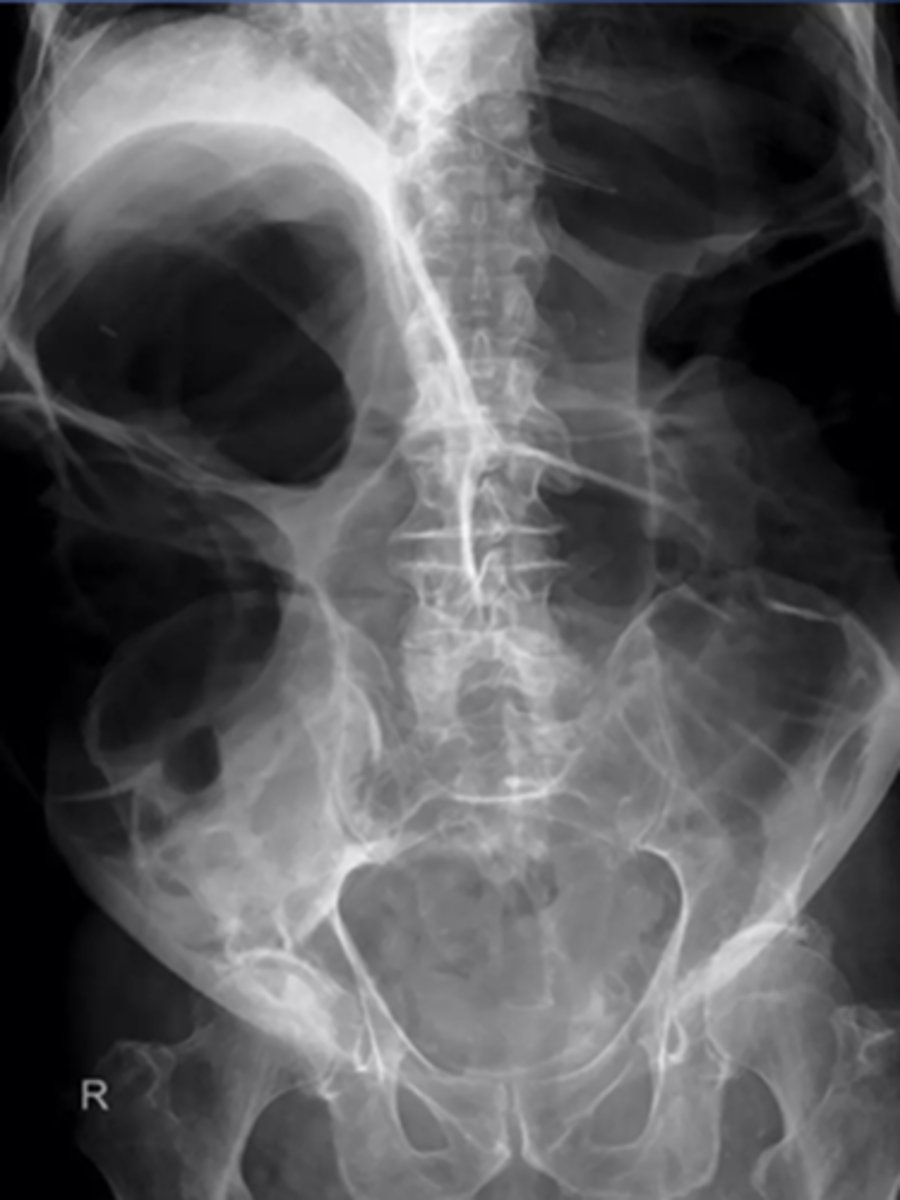

Large bowel obstruction

MC areas of LBO

cecum, hepatic/splenic flexures, sigmoid colon, upper portion of the rectum

_____ valve determines the radiographic appearance of LBOs

ileocecal

competent ileocecal valve (closed loop)

gas and feces can't reflux into small bowel, pressure builds up only in colon

incompetent ileocecal valve (open loop)

gas and fluid reflux backward into small bowel

MC cause of LBO?

tumor